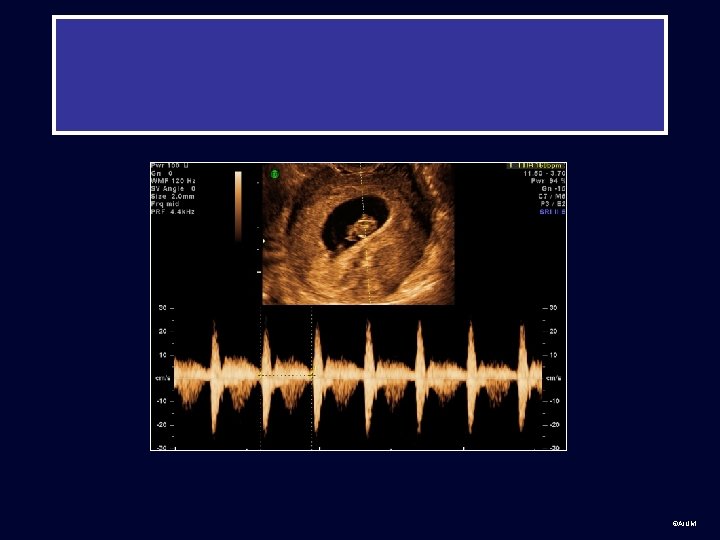

Example of Color and Spectral Doppler Ultrasound § Flow to the transducer is shown in red and away in blue. Cursor Line § The Doppler sample volume (oblique arrow) shows the sampling site for pulsed Doppler interrogation. § The right panel shows spectral Doppler of umbilical artery flow. As the flow is toward the transducer, it is depicted as positive or upward deflections. Umbilical artery Doppler waves ©AIUM